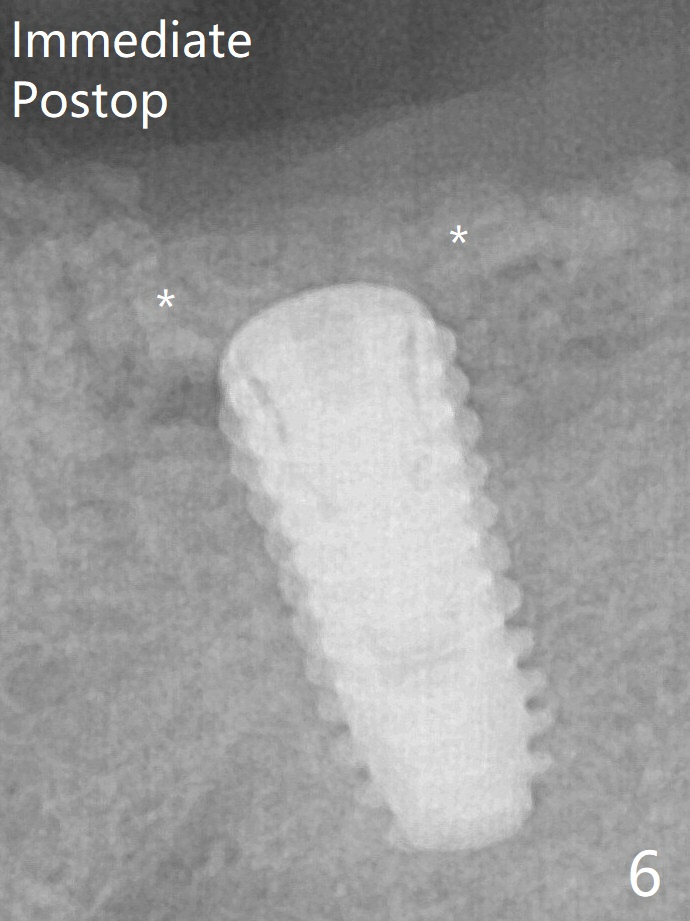

Allograft is placed around the fractured ridge (Fig.6*) before suturing. The ridge appears to have healed nearly 3 months postop (Fig.9). In uncover, the implant plateau is covered with bone; surgical handpiece is used to remove the overlying bone before removing the healing screw. Bone loss in the near future is expected to be minimal if more implants can be placed on the right side. A 5.5x4(4) mm abutment is placed 3.5 months postop (Fig.10).